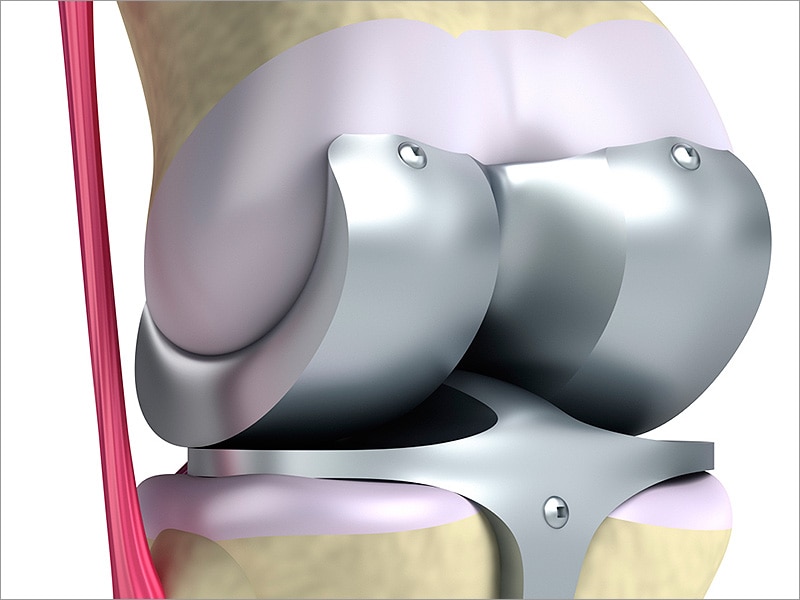

Фотографии и примеры протезирования коленного сустава